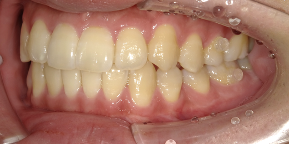

30歳女性のビフォーアフター

| 診断 | 叢生 |

| 治療方針 | 治療方針:インビザラインシステムにて主にIPR(歯と歯の間をわずかに削合してスペースを獲得する方法)を組み込んだ動的矯正治療を行い、叢生を改善後、保定を行う。 |

| 治療費 ※ | 96万5千円(診断、型取り、矯正中のメンテナンス、保定装置を含む料金) |

| 治療期間 | 1年8か月 |